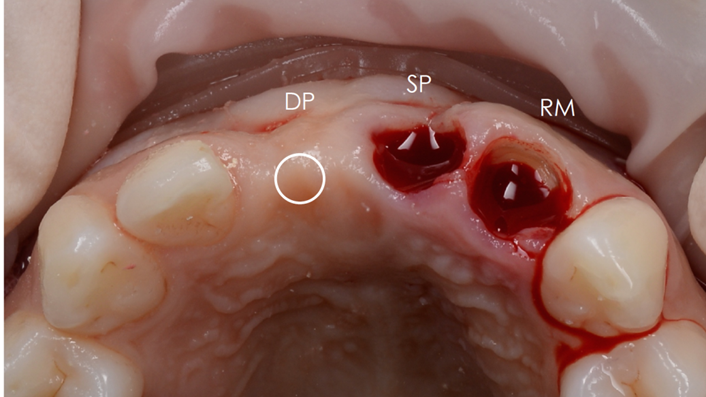

Clinical case: Patient-centered approach: treatment strategy for Root Membrane Technique & delayed implant placement

- Courtesy of Dr. Yoshiharu Hayashi, Japan -

Socket Shield Technique, anterior esthetics, maxillary anterior, esthetic, esthetics, delayed implant placement, socket preservation, AnyRidge, Root Membrane Kit, Root Membrane Technique, Partial Extraction Therapy, PET, esthetic zone, fuse abutment, Dr. Yoshiharu Hayashi,#11,#21,#22

AnyRidge implant system, fuse abutment Root membrane kit, PET Kit